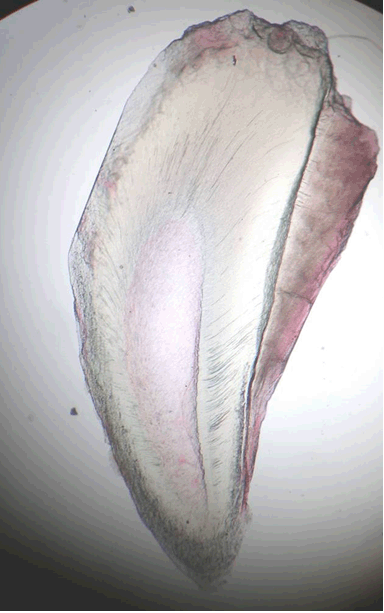

An intraoral periapical radiograph (IOPAR), revealed a single radio-opaque mass lingual to the crown of the deciduous mandibular left second molar, parallel to the long axis to the tooth (Figure 2).

Cursor on image to zoom/Click text to open image

Figure 2: IOPAR showing a single radio-opaque mass lingual to the crown of the deciduous mandibular left second molar.